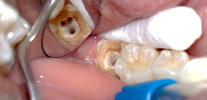

Nell'odontoiatria moderna, viene data preferenza al metodo di estirpazione (estrazione) vitale del "nervo". Durante il trattamento delle forme croniche di pulpite o delle sue esacerbazioni, viene utilizzata solo l'anestesia senza fondi aggiuntivi per la devitalizzazione (uccisione) della polpa.

Numerose istituzioni, in particolare quelle di bilancio, usano ancora pasta di arsenico ("arsenico") o prodotti privi di arsenico per la preparazione preliminare della polpa per la sua estrazione nella terza visita. Anche l'anestesia viene spesso utilizzata, ma la mancanza di tempo, l'incapacità di portare l'anestesia alla perfezione, la fretta o le caratteristiche individuali della mascella di un particolare paziente portano all'incapacità di rimuovere immediatamente il "nervo".

La pasta di arsenico viene posta su denti a radice singola per 24 ore, su denti a radice multipla - per 48 ore. La pasta senza arsenico viene messa a lungo: da 2-3 giorni a una settimana o più. A differenza della pasta di arsenico, non ha un effetto dannoso sul tessuto che circonda la radice, agisce lentamente e delicatamente. Questo è il motivo per cui viene data sempre più preferenza specificamente ai prodotti senza arsenico.